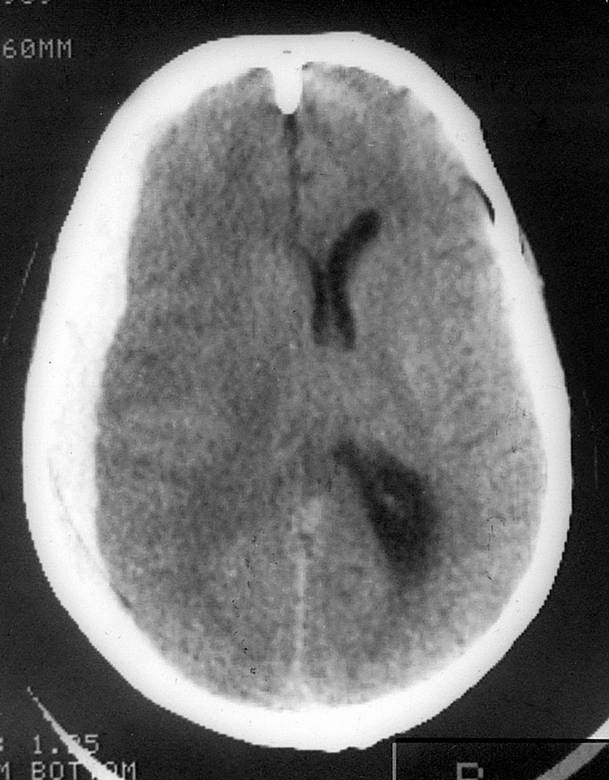

Патологические изменения в правой лобной доле мозга человека

Проведенное магнитно-резонансное сканирование мозга позволило установить, что у всех больных наблюдались серьезные дегенеративные изменения правой лобной доли.